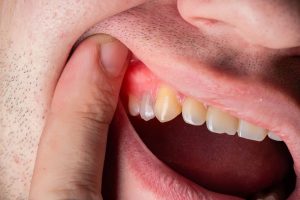

1. Red, Swollen Gums:

• Explanation: Inflammation is a key sign of gum disease. Healthy gums should appear pink and firm, not red and swollen.